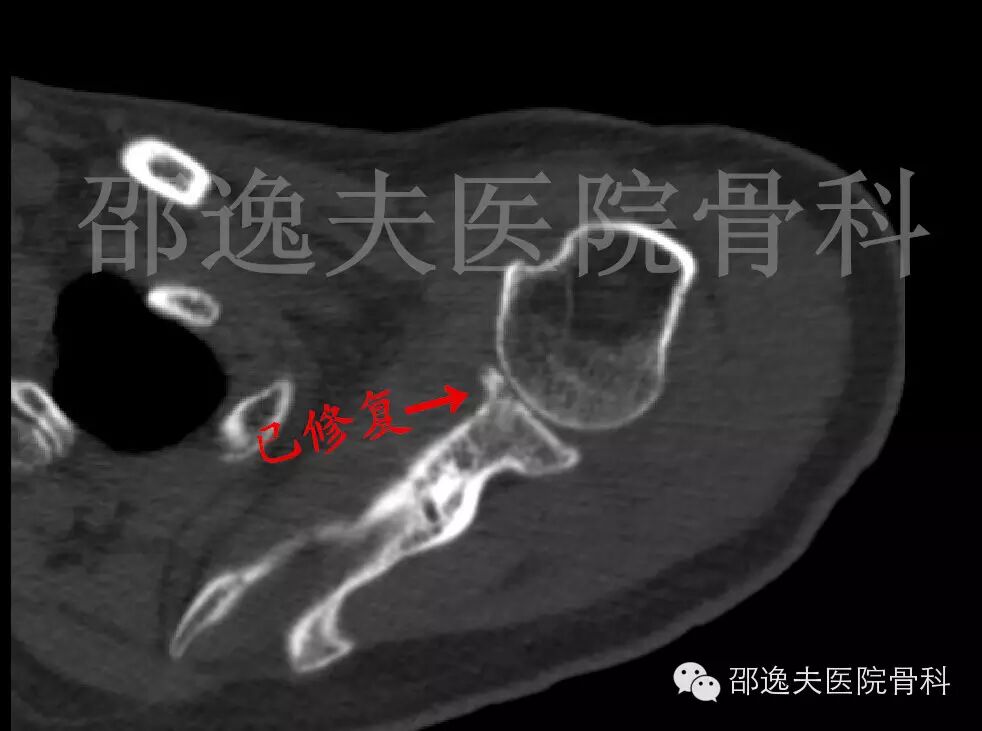

肩部CT扫描

这是典型的骨性Bankart损伤,即指外伤导致肩关节前脱位后与肩关节盂前下缘撞击发生的关节盂前缘撕脱骨折。

术后复查右肩关节CT扫描

检查显示位置良好、固定确实可靠。